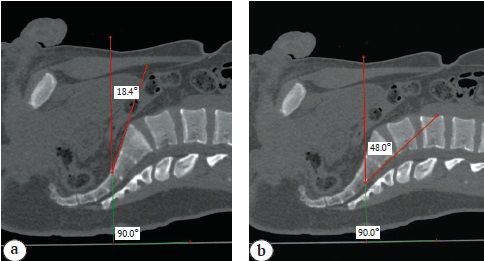

Plotting and measurement of the necessary angles were performed using the reconstructed CT scans in the sagittal view. The true inlet angle was plotted with the apex on the S2-S3 intervertebral disc along the anterior surface, with the ray coinciding with the vertical line drawn to the horizontal surface of the table on which the patient was lying, and the ray connecting the apex of the angle and the anterior edge of the promontory (Fig. 1 a). The super-inlet angle was plotted with the apex of the angle on the S2-S3 intervertebral disc on the posterior surface, with the ray coinciding with the vertical line drawn to the horizontal surface of the table on which the patient was lying, and the ray lying on the posterior surface of the S1-S2 sacral vertebrae (Fig. 1 b).

Fig.1. True inlet pelvic angle (a); super-inlet pelvic angle (b)